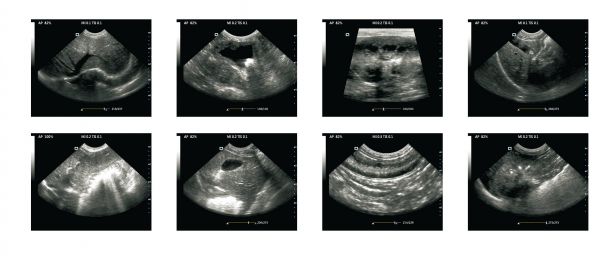

使用甘道夫宠物B超小动物B超可以快速检测猫狗的宠物发情或者怀孕胎子数量以及繁殖障碍疾病,宠物B超检测猫狗等小动物怀孕状态和疾病筛查都是在体外进行,猫狗繁殖育种是一门融合遗传学、营养学、行为学等多学科知识的综合性技术,其科学性和规范性直接影响着后代的健康与品质。随着宠物经济的蓬勃发展,越来越多家庭将猫狗视为重要家庭成员,这使得科学繁殖技术的重要性日益凸显。甘道夫宠物B超小动物B超为了让宠物更好健康成长免费提供宠物B超技术培训服务 猫狗小动物B超超声图像分析欢迎大家前来交流学习。宠物B超机多少钱,全国宠物B超厂家价格报价,宠物B超品牌厂家,小动物B超多少钱,小动物B超厂家价格报价快来咨询甘道夫宠物B超咨询

(1)使用甘道夫宠物B超小动物B超可以快速掌握猫狗小动物繁殖规律,犬属于季节性单次发情动物,母犬每年发情1-2次,发情期持续21天左右,分为发情前期(7-10天)、发情期(5-9天)和发情后期。金毛、拉布拉多等中型犬成熟期约8-12个月,建议配种年龄在18个月后以确保骨骼发育。怀孕平均63天,使用宠物B超小动物B超在狗怀孕7-10天即可快速筛查出来狗狗是否配种成功和胎子数量,掌握每胎产仔数因体型而异,吉娃娃通常1-3只,而大丹犬可达8-12只宠物繁殖是一个涉及生物学、行为学和饲养管理的复杂过程,不同物种的繁殖周期差异显著,且受遗传、环境、营养等多重因素影响,母犬怀孕期需增加30%热量摄入,专业繁殖者会进行环境丰富化训练。幼犬早8周龄方可离窝,过早分离会导致行为异常风险增加3倍。

宠物B超小动物B超检测猫狗怀孕方法图像分析

(2)使用甘道夫宠物B超小动物B超快速检测猫咪怀孕规律,猫是诱导排卵动物,母猫在光照充足的季节(春夏季)会周期性发情,每次持续4-6天,若无交配可间隔2-3周重复发情。猫等品种成熟较早(4-6个月),但过早繁殖易导致难产。怀孕期约58-67天,使用宠物B超小动物B超在猫咪怀孕7天以后即可快速检测出来胎子数量,平均每胎4-6仔,未绝育母猫理论上年产仔可达12-18只。 宠物B超机价格小动物B超品牌厂家报价

(3)使用宠物B超可以快速筛查出优良品种的宠物,人工授精技术的突破极大拓展了优质基因的传播范围。冷冻精液可保存优秀种犬遗传物质长达15年,胚胎移植在稀有品种保护中展现出特殊价值。成功完成跨洲际猫胚胎移植,将孟加拉豹猫胚胎植入代孕家猫子宫。这种技术为濒危猫科动物保护提供了新思路,但代孕母体的选择需严格匹配体型差异,通常受体动物体重应与供体相差不超过20%。